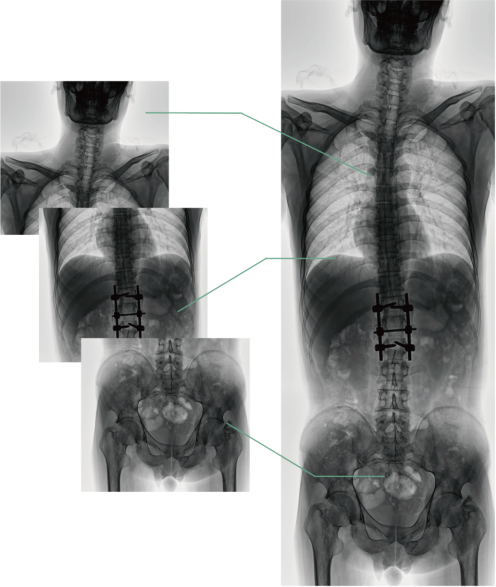

四、图像自动拼接

图像自动拼接功能实现全脊柱、全下肢全景摄影,解决在观察颈椎至尾椎的脊柱侧弯或其他病变时不能一次成像的问题,能够直观的显示脊柱和下肢的整体解剖形态及侧凸部位。